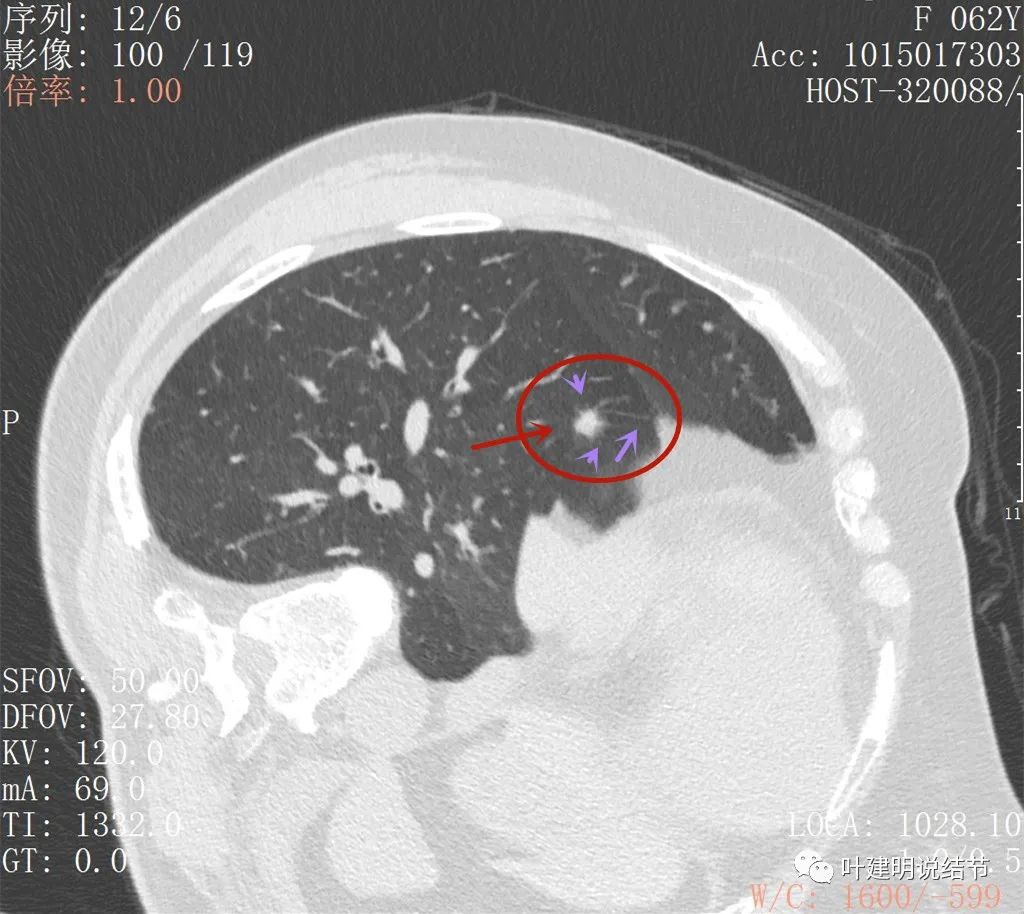

上图也是较为典型的恶性样子,有血管征,有边缘细锯齿状,且存在2年多不吸收好转,也不钙化或成疤痕样收缩